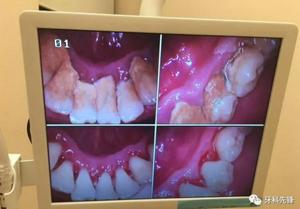

“我知道牙結(jié)石有種種危害,但是我以前沒有意識到,現(xiàn)在牙齒松啦!靠牙結(jié)石撐著還能再用一段時間,突然給我洗掉牙結(jié)石牙齒會不會讓我的牙齒更加松動呢?”

臨床上確實存在這樣的情況,但是作口腔醫(yī)生,我為一名可以負責(zé)任的告訴大家,如果不清除掉牙結(jié)石后果會更加嚴重,甚至有脫落的風(fēng)險。原理是什么呢?因為牙結(jié)石、牙菌斑的破壞能力是極其強大的,只要它存在就會一直不斷的刺激壓迫牙齦,時間久了則會導(dǎo)致牙齦紅腫出血、牙槽骨吸收、牙齦萎縮、牙齒松動甚至脫落等情況,這是一個緩慢發(fā)展的病變過程,單純的靠牙結(jié)石撐住牙齒不讓其出現(xiàn)病理性移動從根本上講是極其不現(xiàn)實的,有點兒“掩耳盜鈴”的意味,不僅撐不住反而會加快牙齒松動、脫落。很可怕吧,尤其是對于我們成年人來說,現(xiàn)有且僅有的一副恒牙竟然還被牙結(jié)石牙菌斑禍害成這個樣子,應(yīng)該算是一種不幸吧!